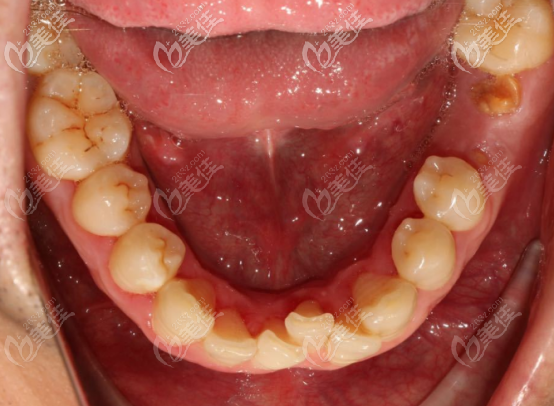

術(shù)前口內(nèi)照

設計方案:拔出埋伏牙,先用矯治器擴大牙弓的寬度,給之后的矯正留足空間,設計矯正器的時候,留出要種植區(qū)的間隙,并且給過小牙留出貼面的寬度,調(diào)整牙齒中線偏移的問題。